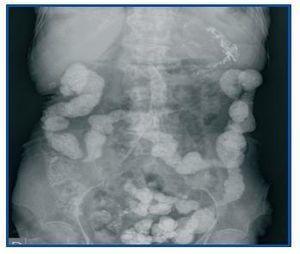

Figure 2. Simple abdominal radiography without contrast showing multiple onecentimetre sized opaque points irregularly distributed along the contour of the colon, which are lanthanum deposits in the diverticuli.